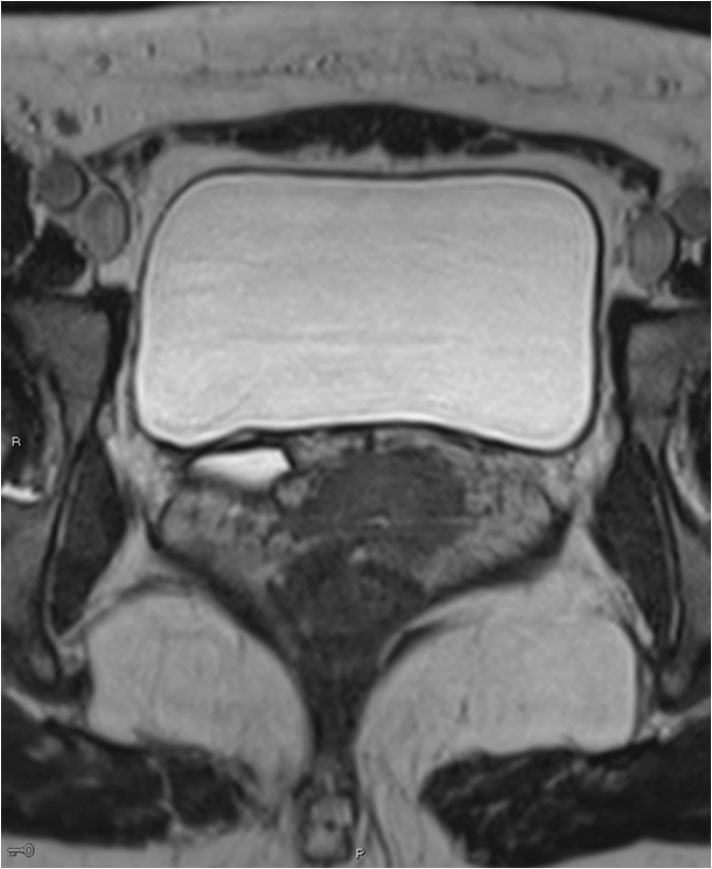

CT av urinveier ble utført, men det var ikke mulig å gi noen konklusjon med hensyn til ektopisk munnende ureter. Det ble derfor utført MR av urinveiene. Det forelå dobbeltanlegg på høyre side med et lite øvre anlegg og et dilatert ureter (fig 1). Ureter forløp dilatert mellom urinblære og vagina og munnet ut ektopisk nær urethras utmunning (fig 2).

For å identifisere dobbeltanlegg og ektopisk munnende ureter på CT forutsettes tilstrekkelig funksjon og kontrastutskilling fra det øvre anlegget, noe som ikke var tilfellet for denne pasienten. Ultralyd kan identifisere dilatert, ektopisk ureter, men det kan være vanskelig og krever som regel spesiell oppmerksomhet. Vår pasient var henvist med spørsmål om kolelitiasis og pyelonefritt, og det ble ved rutinemessig vurdering av urinveiene ikke oppdaget patologi. Høyoppløselige væskesensitive MR-sekvenser i volumopptak gir gode forutsetninger for å identifisere ureter og følge ureters forløp. I det lille bekken er MR bedre egnet enn CT, men mer tidkrevende. Det ble utført dedikerte høyoppløselighetsserier i bekkenet supplert med mindre detaljrike sekvenser over øvre urinveier. Det ble ikke benyttet kontrastmiddel under MR-undersøkelsen. Barnelegene bruker MR som primær modalitet ved mistanke om ureteral ektopi.

Årsaken til pasientens vedvarende problem med urinlekkasje var altså et ektopisk munnende ureter (fig 3).